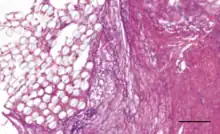

PET artificial ligament coated with hyaluronic acid coating. Collagen tissue infiltration is evident.

Coatings have been added to artificial ligaments to improve their biocompatibility. 58S bioglass and hydroxyapatite coatings have been shown to improve osseointegration and cellular activity in vitro and in animal studies[3] when deposited onto PET ligaments using the soaking method.[2][3] Hydroxypropyl cellulose surface treatments have been shown to improve osseointegration for PET ligaments in animal studies.[2] Uncoated PET is hydrophobic, so coatings are designed to improve hydrophilicity.[3] Hyaluronic acid coatings can reduce hydrophobicity and have been shown to reduce scar tissue formation and inflammation in vivo.[3] Hyaluronic acid and chitosan composite coatings can be deposited onto artificial ligament surfaces by the layer-by-layer technique, and they have been shown to enhance new bone formation at the ligament interface in mice.[9] The chitosan is used to reduce hydrophobicity and improve osseointegration and mineral deposition, while the hyaluronic acid promotes cell differentiation and growth.[9] Poly(sodium styrene sulfonate) coatings have been shown in animal studies to improve knee functionality and mimicry of the native ACL.[2][13]